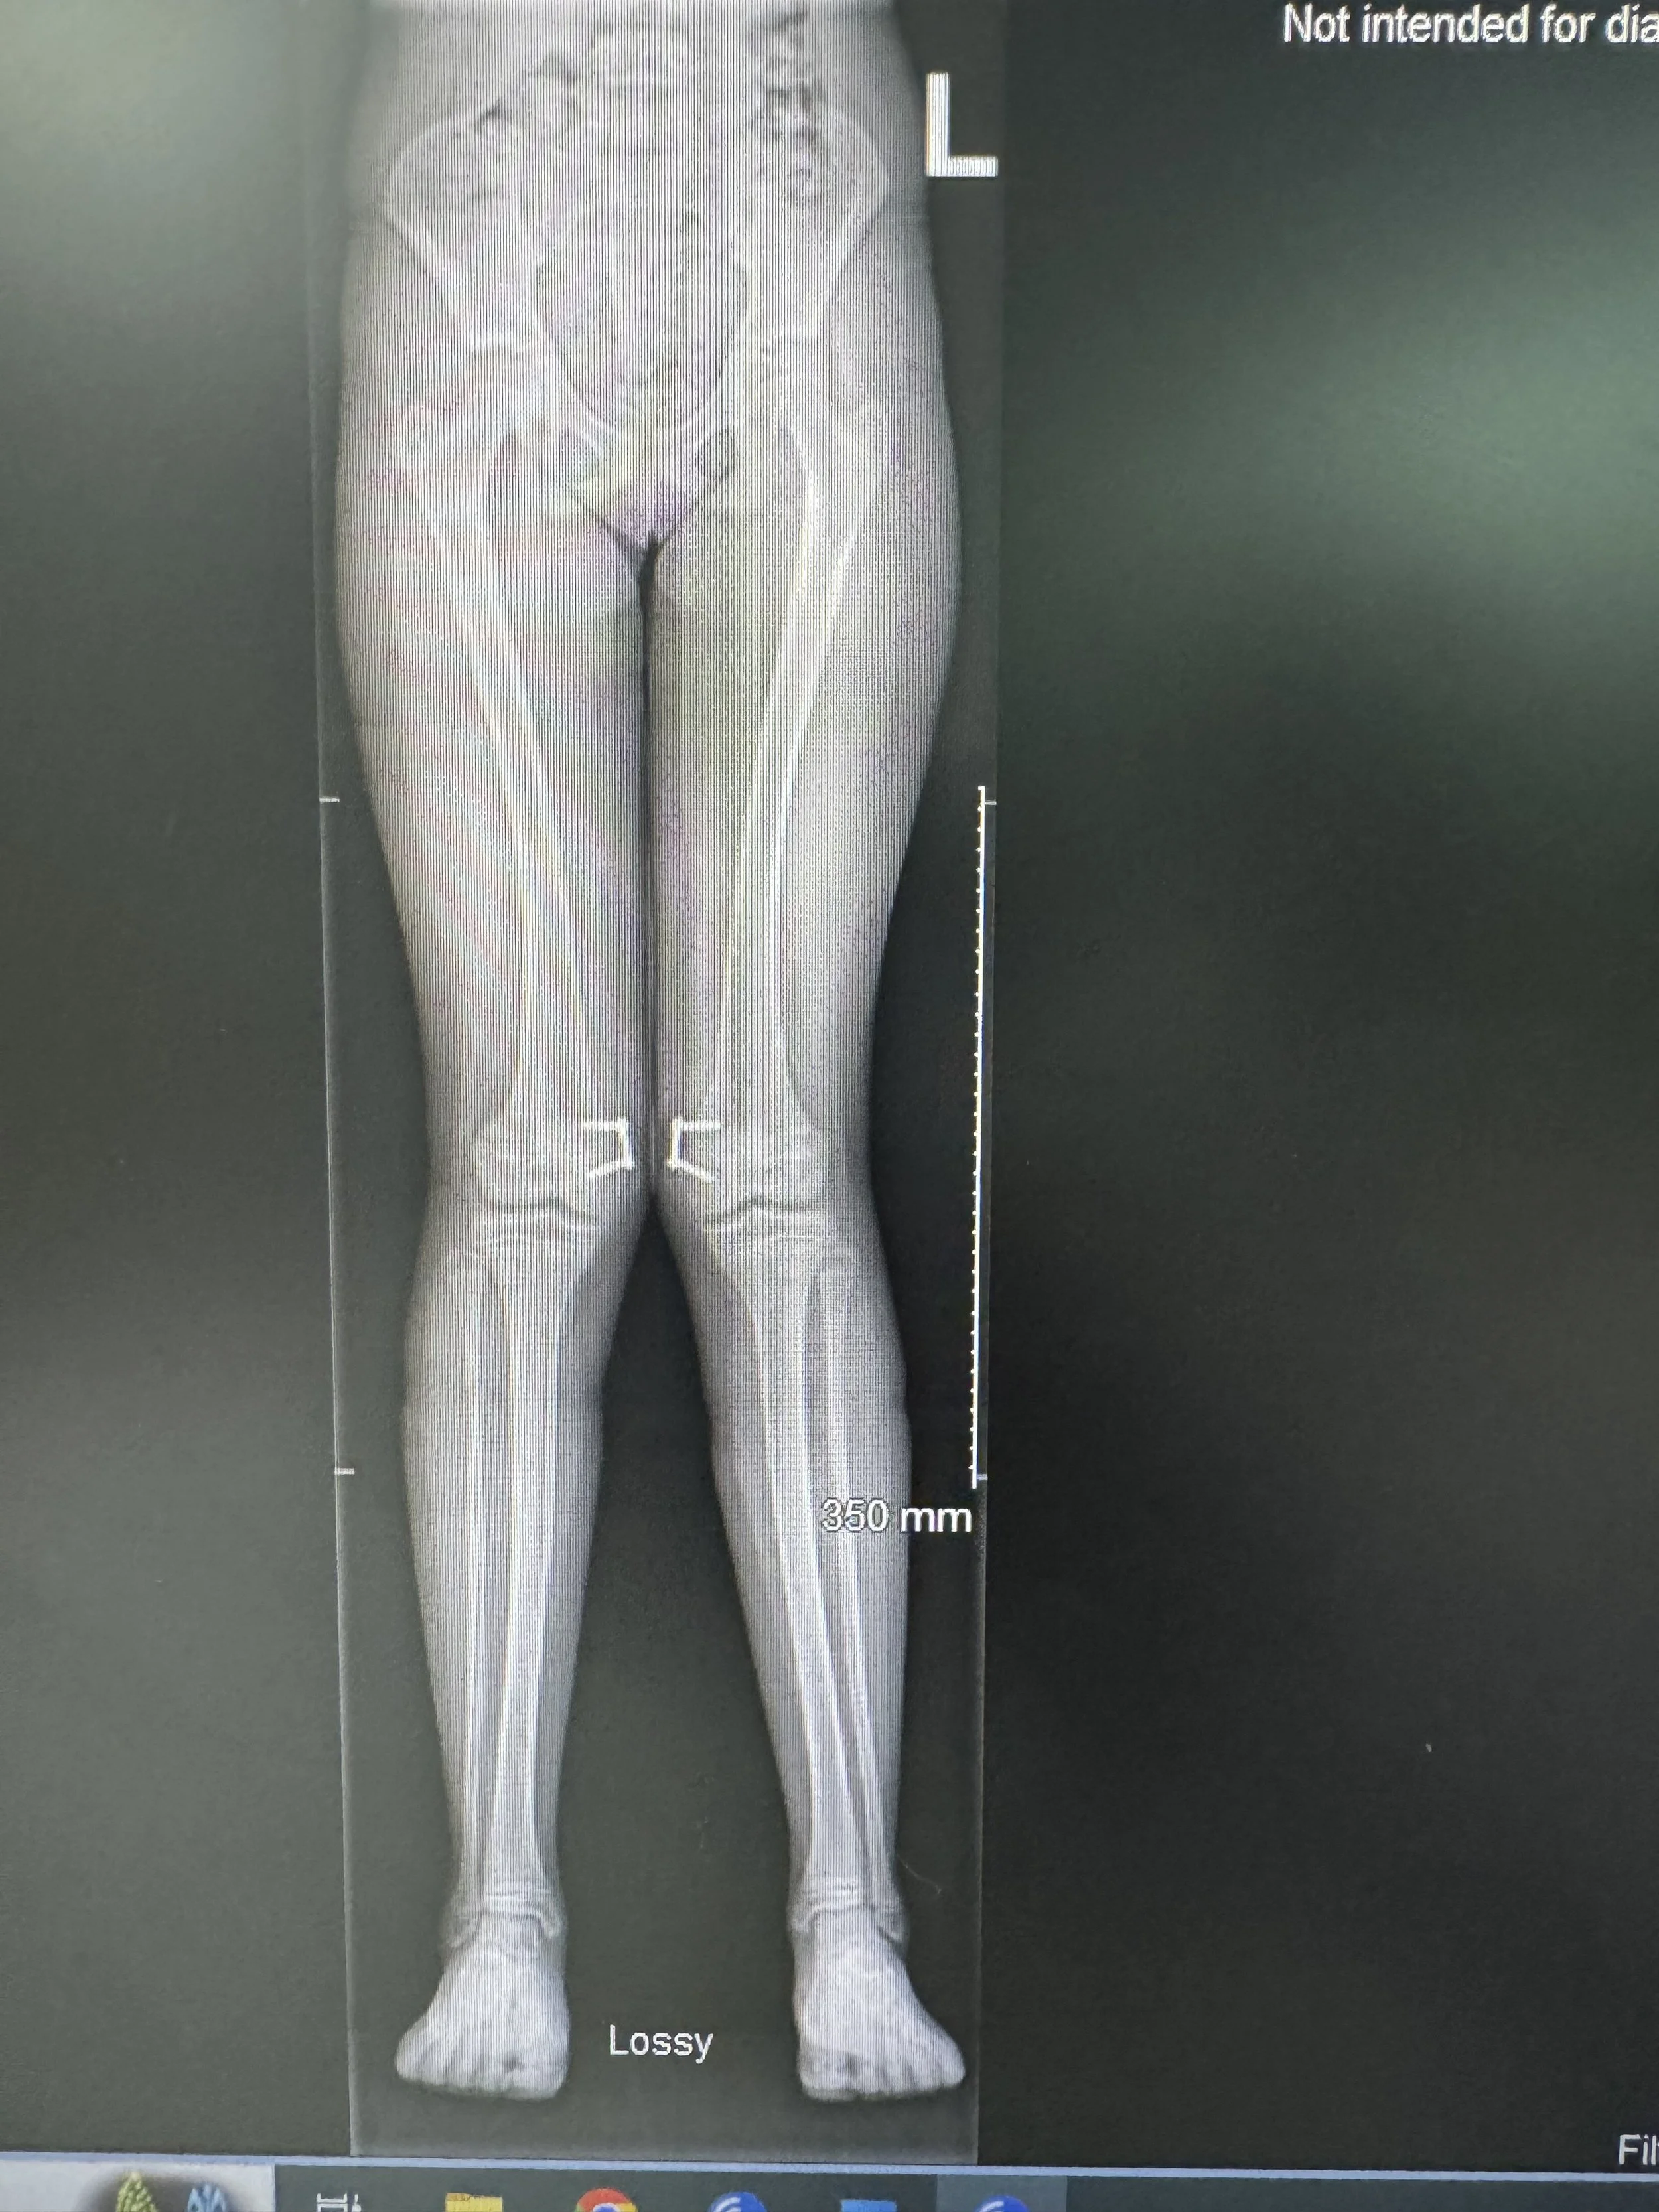

Genu valgum after femoral 8 plate correction

Same patient as above 12 months after correction with femoral 8 plates by Professor Gupte